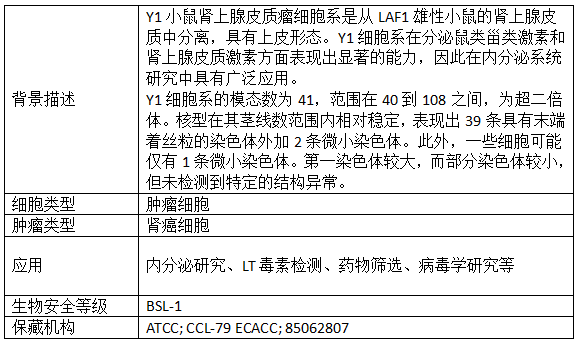

产品信息: